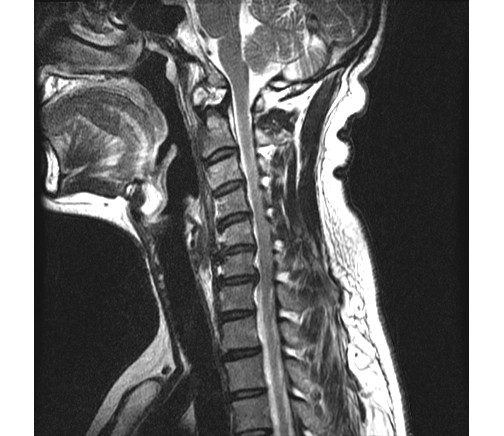

2013 2 ʴٸ 鼭 ѵ ӵǾ ȼ ִ 湮Ͽ а˻(MRI) ް, 㸮ũ Ű ִٴ ô ڼ, Ű漺ü ް ũ ٰ ĥ ڰ ʰ ̿ ణ ְ, ȿ Ÿ ĥ ȣ ٽ ġḦ Ҵ **** 湮Ͽ x-̿,MRIԿ غ ʿ Ʒ(4.5.6.7) 3 ũ Ƣ Ű ִٴ ¿ϴ. ſ Ͽ ٰ մϴ. ϴ Űֻ ġ Ÿ ¿, Ϻ ߷° ġḦ ̾ϴ. ġ Ŀ ° ȭǸ ñδ ھƼ ߺκ ִ ƾ ȴٰ ߽ϴ. ũ 500 ,ġ 2,500 ȴٰ ߽ϴ. üϿ콺 縦 ϴ 忡 Ŀ üϿ콺 ãƾ ߰ ϴ ϸ鼭 ͳݿ ڷḦ ã ߿ ڸǥغ ˰Եǰ Ͼ ʴ ʱ۵ 鼭 ʱ۵ ܼ ȸ Ͽ ڸǥغ ߽ϴ. ߰ ȸ ȭ ʰ Ͽ غ ξ ϰ پϴ. ڰ ʹ Ͼ ٽ þ ִ ȸ ȣ ȴ Ͽε ұϰ ݹ ȭ Խϴ. ̰ ð ϰ ʰ Ȱ ɴ ڼ ϴ. ϴ ÿ پ ϴ. ͳݿ ** ˷ֽôµ ϰ ƮĪ ̾ϴ. ȸ ó Ȯϰ ϴ Դϴ. ȭȭ ˷ֽôµ Ȯϰ ִ ͵ ű߽ϴ. ǻ ֽð ı ̶ ϴ ϸ鼭 ߰ 30ʾ ϶ ߽ϴ. ῡ ٽϰ ƮĪ ȿ ϰ ٲ۴ٰ ϼ̽ϴ. 鿡 ϴٰ ְų ִ پ ̶ ϸ ȭֽŴٰ ߽ϴ. ̰ͱ ħ ̾ϴ. ῡ Ϸ ϰ ῡ ȸԲ ڷ 帰 Դϴ. ȸԲ ˷ֽ ϸ鼭 ƴ غ ° Ǵ ȭ Դϴ. õ Կ ſ 鿡 ϴ ֽ ڼ Ϸ ϴ, ణ Ÿ° ʹٰ ߽ϴ. ʰ ,Ŀ ƿͼ õ κ(12).Ӹ(8) غ Բ , ȵ ణϰ Ÿ., ⺻ Ӹе 9 غ 30 ǻϴ. Ӹκ 9е ؼ ϰ ֽϴ. ߽ϴ. ȭ ּ̽ϴ. ǻͿ ɾƼ mriϰ Ͽ 帮 Ű澲ٰ ٽ ͽϴ. ȸԲ ʰ ǻ ϴ¹ ˷ֽʴϴ. ǻ տ Ȳ ʰ ɴ ڼ ٲٴϱ ϴ. űԿ ڼ ߿ ƮĪ ü ߿伺 ű ȵ ߽ϴ. ʰ ȸϴ е ʱ۵ ó Ե Ͼ ̷ο Բ ʾƵ ǰڴٴ 밨 ϴ. mri ½ϴ. ȸԲ Ȯϰ Ǵϰ ٽ ȮҶ Ʒ mri øŴϴ. ø Ȯֽð Ź帳ϴ. ---------------------------------------- -- û Ȯϱ Ͽ mri øϴ. |